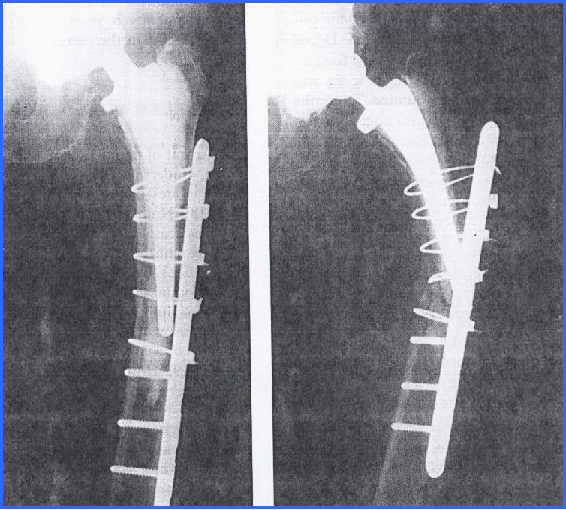

髓外固定:(一)环扎固定

一般用于处理假体稳定的假体柄周围的螺旋形或长斜形骨折(机械力量差,单独使用的情况很少,一般联合钢板螺丝钉、异体骨板或翻修假体使用);

对于在植入假体柄时发生在股骨近端的裂隙骨折,可考虑此固定方法

髓外固定:(二)钢板螺丝钉

适用于假体无松动、假体中立位(无外翻)的骨折

成功的关键在于钢板必须和假体末端有部分重叠

假体与钢板重叠部分的固定

环扎方法

特殊钢板

·Ogden钢板 :1988年Zenni :19例 ,17例获得良好临床结果

·Dall-Miles钢板 :2001年Venu :13例 ,10例成功,假体中立位;3例 失败,假体已松动或初始位置为内翻位

·Mennen钢板 :2002年Noorda :36例 ,31%出现了机械固定失败,28%骨折不愈合

髓外固定:(三)异体皮质骨板

Emerson:在8.4个月时异体骨板和宿主骨愈合,愈合率96.6%

Haddad:2002年,对40例假体固定良好的股骨假体周围骨折使用了异体骨板固定,骨折98%愈合,而且在术后第一年内有典型的宿主骨异体骨愈合发生